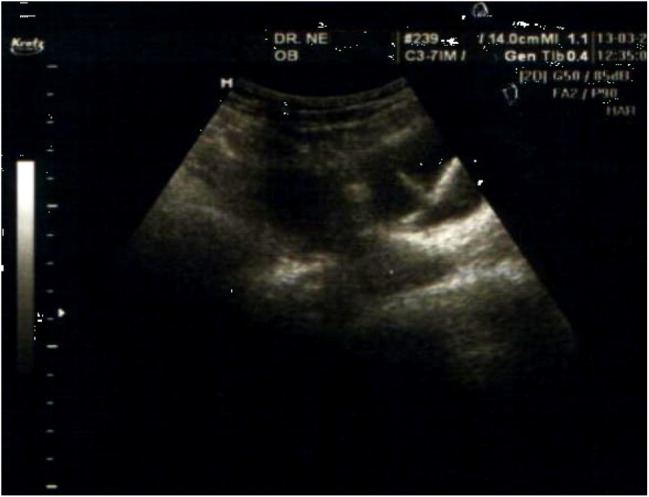

Case presentation: A 35 year-old female 5 gravid, 4 para has been benefited from intrauterine contraceptive device (IUCD) 5 years ago, she was presented to gynecological consultation for chronic pelvic pain with urinary symptoms. There was history of a good IUD insertion 5 years ago, considered expelled after one month of its pose. Physical examination was normal, but a pelvic ultrasound and a plain abdominal radiography allowed the detection of an IUD outside the uterine cavity, but inside bladder. A diagnostic and therapeutic cystoscopy was performed, and the IUD with calculus was successfully removed. There were no postoperative complications.